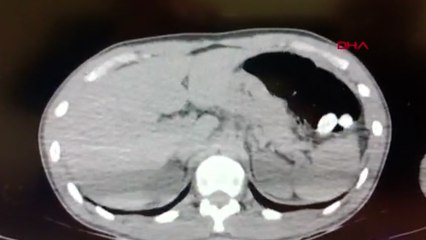

Bayburt'ta polis ekiplerinin durumundan şüphelendiği kişinin midesinden 588,55 gram uyuşturucu çıktı.br İl Emniyet Müdürlüğü Narkotik Suçlarla Mücadele Şubesi ekipleri, kent merkezinde şüpheli hareketlerde bulunan yabancı uyruklu D.A'nın yanına gitti.br Üst aramasının ardından Bayburt Devlet Hastanesi'ne götürülen şüpheliye yapılan tetkiklerde, midesinde kapsül halinde haplar bulunduğu belirlendi.br Zanlının midesinden, tıbbi müdahale ile 588,55 gram metamfetamin çıkarıldı.br Gözaltına alınan zanlı, emniyetteki işlemlerinin ardından sevk edildiği hakimlikçe tutuklandı.